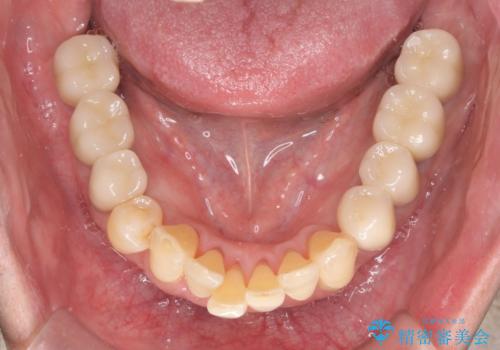

インプラント・ブリッジ補綴を含む、歯周病全顎治療

長期間にわたる治療後、歯に対する意識も大きく変わりプラークコントロールも非常に良くなりました。

数ヶ月に一度のチェックをしっかりと行い、ブリッジ・インプラントが長期間使用できるようメンテンスを行っていきます。